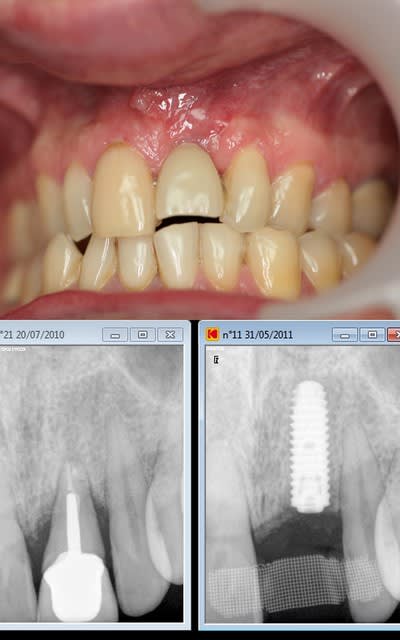

je rebondis sur ton titre" ne jamais faire de jolie provisoire", car ça me rappel une patiente.

25 ans, implanté en 2009

extraction-Summers-implantation- MCI sur une "jolie" provisoire avec du composite montée sur un pilier en pick...

(dernière photo contrôle à 15jours)

je l'ai rappelé il y a un an; pas de nouvelles, la provisoire doit lui convenir...

ps: c'est peu être le seule implant dont j'espère qu'il tombera. NA!

conclusion: ne jamais faire de jolie provisoire